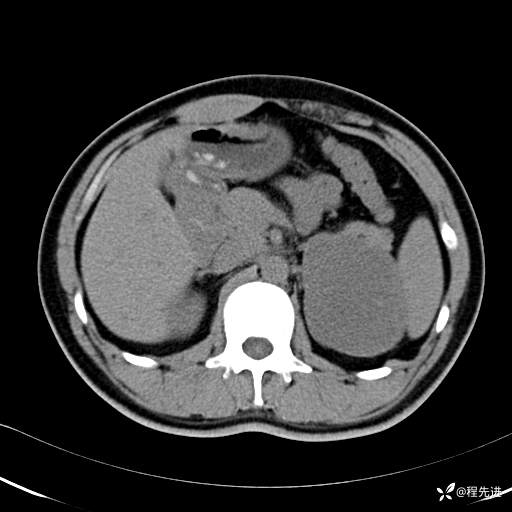

CT平扫:(CT值:平扫,27HU,动脉期,27HU,门静脉期,31HU,平衡期,32HU)

CT增强:

门静脉期:

平衡期: